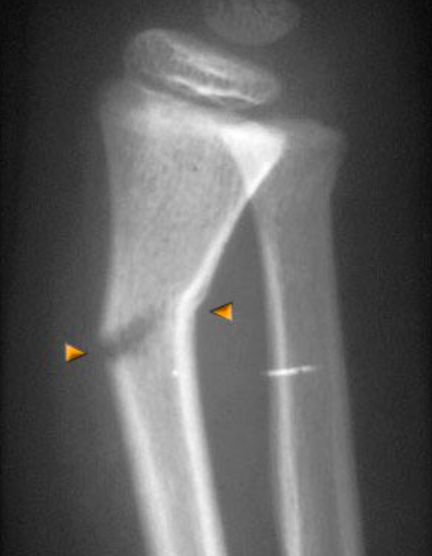

الفرق الآخر والمهم للغاية بين عظم الطفل وعظم البالغ هو وجود مراكز النمو في عظم الطفل وعدم وجودها في عظم البالغ بعد اكتمال نموه. مراكز النمو هي المسؤولة عن ازدياد طول العظم في فترة النمو...

مراكز النمو الموجودة في عظم الطفل تقع عند نهايات العظم بالقرب من المفاصل كما هو موضح في الصور . تظهر في الأشعة كخط أسود منتظم في أطراف العظام الطويلة ..

قوة التحمل الكامنة في مراكز النمو لمقاومة الإصابات هي أقل من قوة بقية العظم، لذلك قد تحصل كسور الأطفال في مراكز النمو نفسها كما هو موضح

كسور مراكز النمو تحتاج إلى عناية خاصة من قبل الطبيب المعالج ومتابعات على مدى بعيد للتأكد من سلامتها وعدم تأثرها من الإصابة...

قد تتسبب كسور مراكز النمو بضرر كامل او جزئي في مركز النمو.

إذا تضرر كامل مركز النمو سينتج عن ذلك توقف للنمو في العظمة المصابة مما سيتسبب في قصر متزايد في العظمة المصابة بالمقارنة مع الطرف السليم الذي يكمل نموه بالمعدل الطبيعي. الفارق النهائي يعتمد على عمر الطفل وقت الإصابة

في حال كان الضرر في مركز النمو جزئيا، فالجزء المتبقي من مركز النو سيتسبب بنمو غير متماثل في العظمة ينحرف بها عن استقامتها الطبيعية.